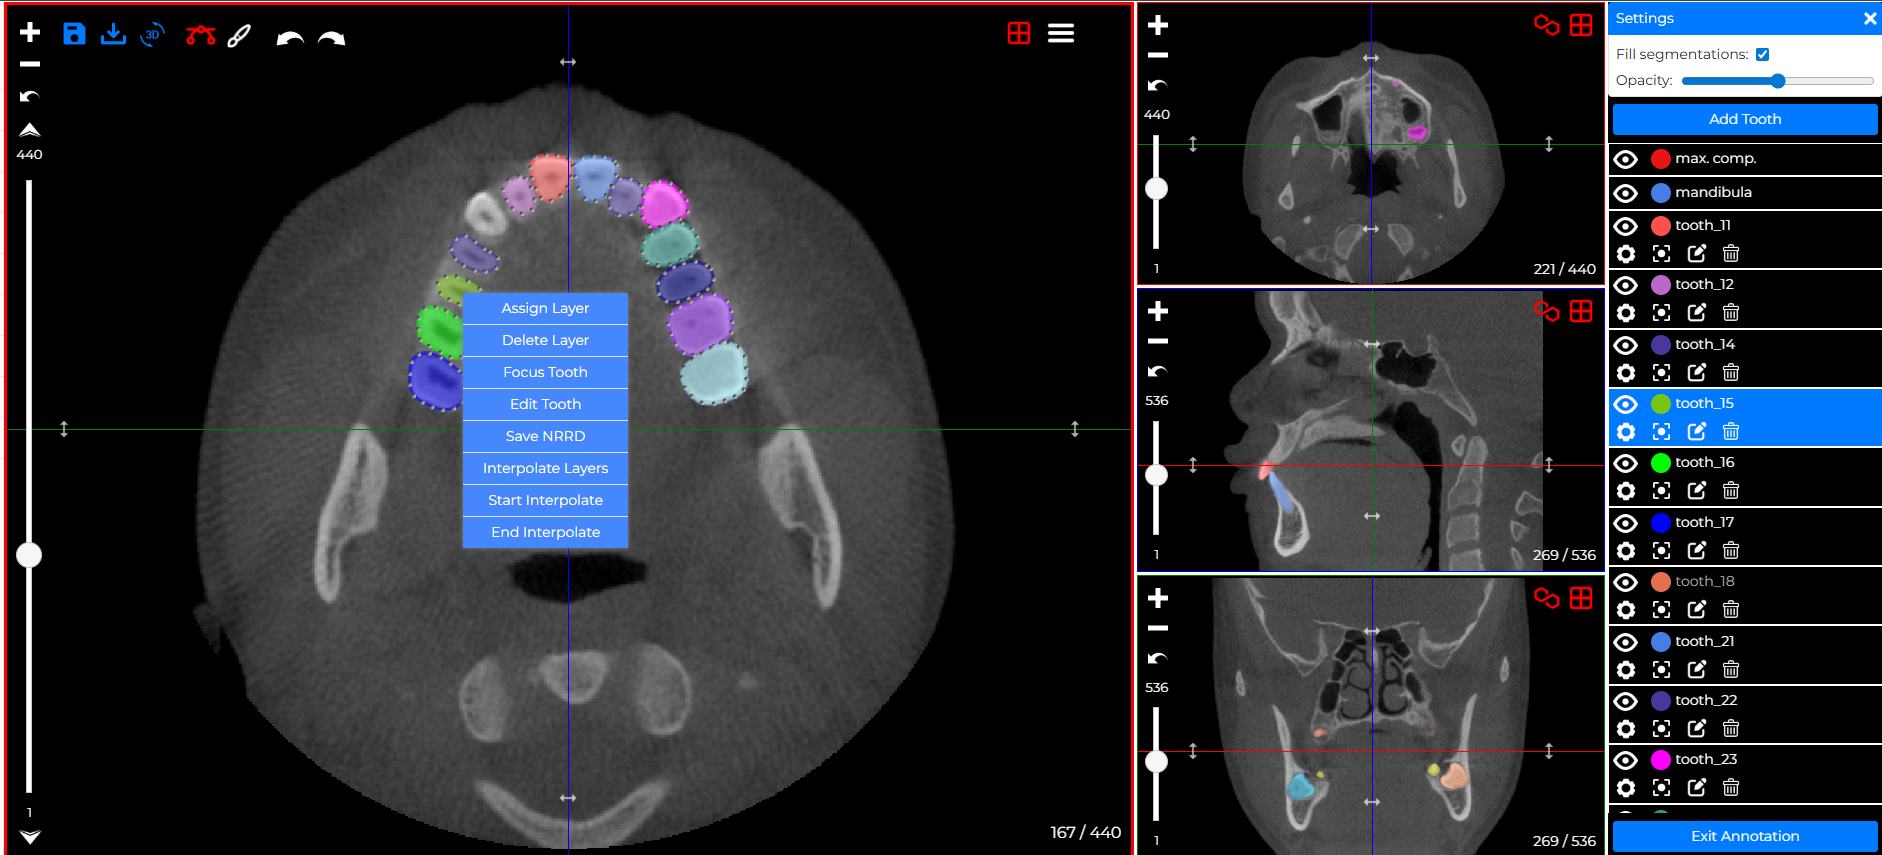

Interpolation

The new Interpolation feature automatically generates tooth layers between defined slices, eliminating manual slice-by-slice drawing. This makes tooth annotation for 3D models faster, more consistent, and saves significant time when creating or adjusting teeth.

How Does It Work?

For an existing tooth, open the annotation menu, select Interpolate, define the start and end layers, and click End Interpolate to automatically generate all layers in between.

For a new tooth, create the first layer, start interpolation, add or clone the second layer on another slice, and end interpolation to let the system build the full segmentation automatically.